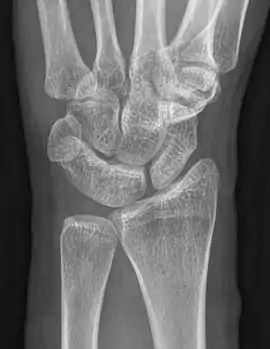

| An example of a lunotriquetral coalition, the most commonly fused carpal bones | |

The lunate and triquetral bones are the most common carpal bones to fuse together, resulting in a lunotriquetral coalition in 1% of people. 60% of patients with a lunotriquetral coalition will have it bilaterally.[1] Among isolated incidents the capitate and hamate bones are the next most common to fuse followed by the pisiform-triquetrum, trapezium-trapezoid, scaphoid-capitate, and triquetrum-hamate.[3]